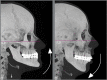

Introduction: The smile arc is an esthetic parameter that has been better investigated by Orthodontics after the "new esthetic paradigm". Its diagnostic evaluation and inclusion in the objectives of orthodontic planning has become fundamental for professionals seeking for more beautiful and youthful natural esthetic outcomes.